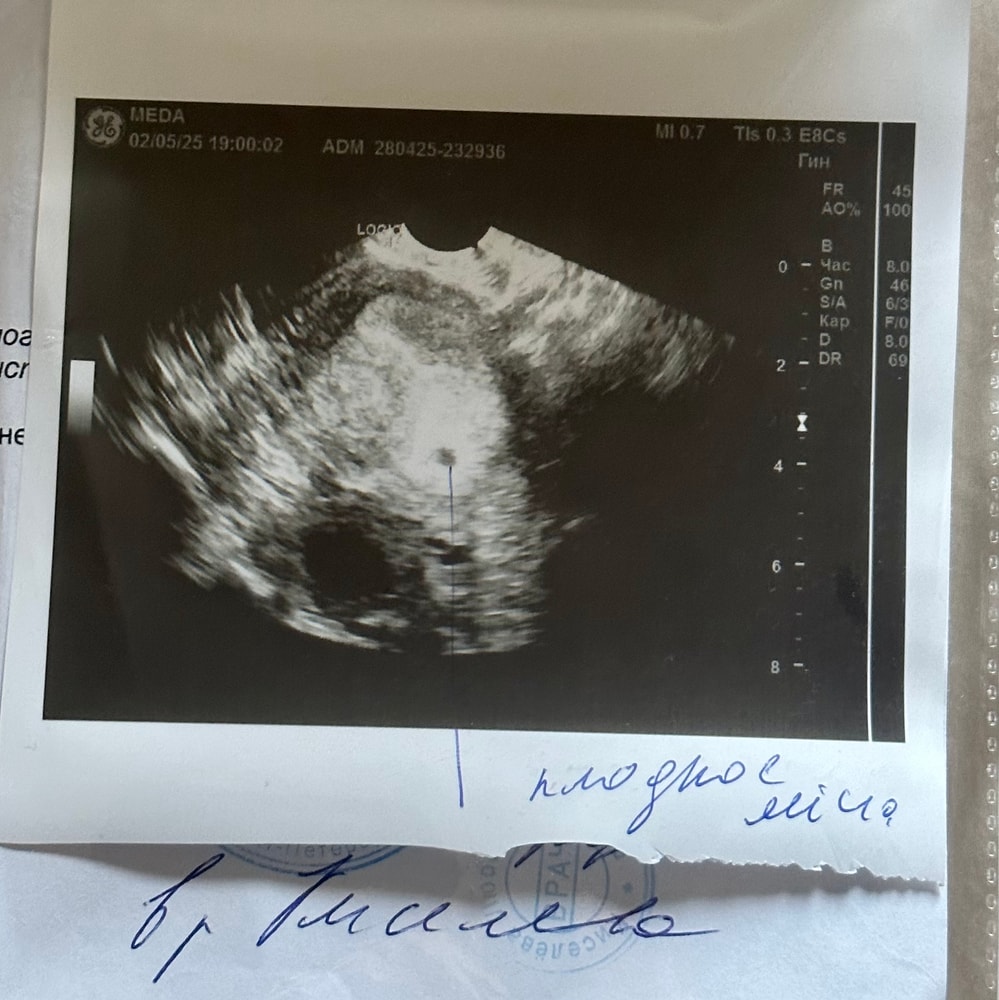

УЗИ, КТГ, доплерХодила сегодня на узи, хгч по подсчетам 1000+ должен был быть, овуляция была поздняя

увидели пя 5 мм, эндометрий 14 мм и желтое тело 16 мм

Пугает, что желтое тело маленькое и свободная жидкость в незначительном количестве и ощущение, что с размером ПЯ спутали, так как на снимке кажется ещё меньше